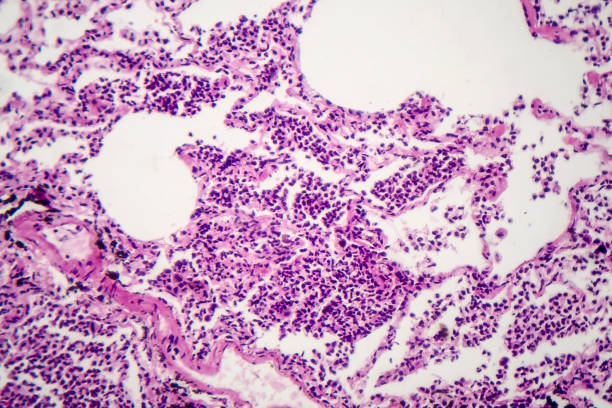

폐섬유화증은 폐조직 내 결손 및 염증에 의해 섬유화 과정이 일어나서, 건강한 폐조직이 염증과 섬유화에 대한 대체물질로 치환되는 질환입니다. 이로 인해, 섬유화된 조직은 신축성이 없고, 호흡기능이 저하됩니다. 따라서 다른 질병과 마찬가지로 초기에 적절한 치료를 받는 것이 중요하기 때문에 이번 시간에는 폐섬유화로 인한 증상들에 대해 정리해보겠습니다.